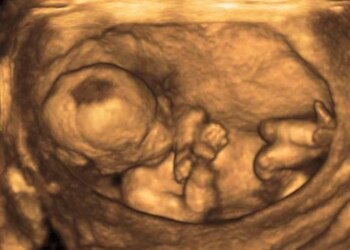

Los legisladores eslovacos tienen previsto debatir el viernes una propuesta de ley que obligaría a las mujeres que quieren abortar a hacerse primero un ultrasonido y escuchar los latidos del embrión o del feto, una medida que muchos grupos han denunciado como un paso atrás para los derechos de las mujeres.

El proyecto fue presentado por tres miembros del conservador Partido Nacional Eslovaco, que sostienen que su objetivo es “asegurar que las mujeres estén informadas sobre la etapa actual de su embarazo” antes de interrumpirlo.